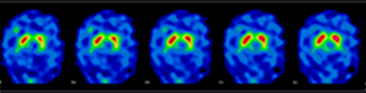

La figure 2 illustre un Datscan normal avec fixation du traceur au niveau de la tête des noyaux caudés et des putamens, se traduisant par une image en «double virgule symétrique» en regard des noyaux gris centraux (fig. 2).

Figure 2